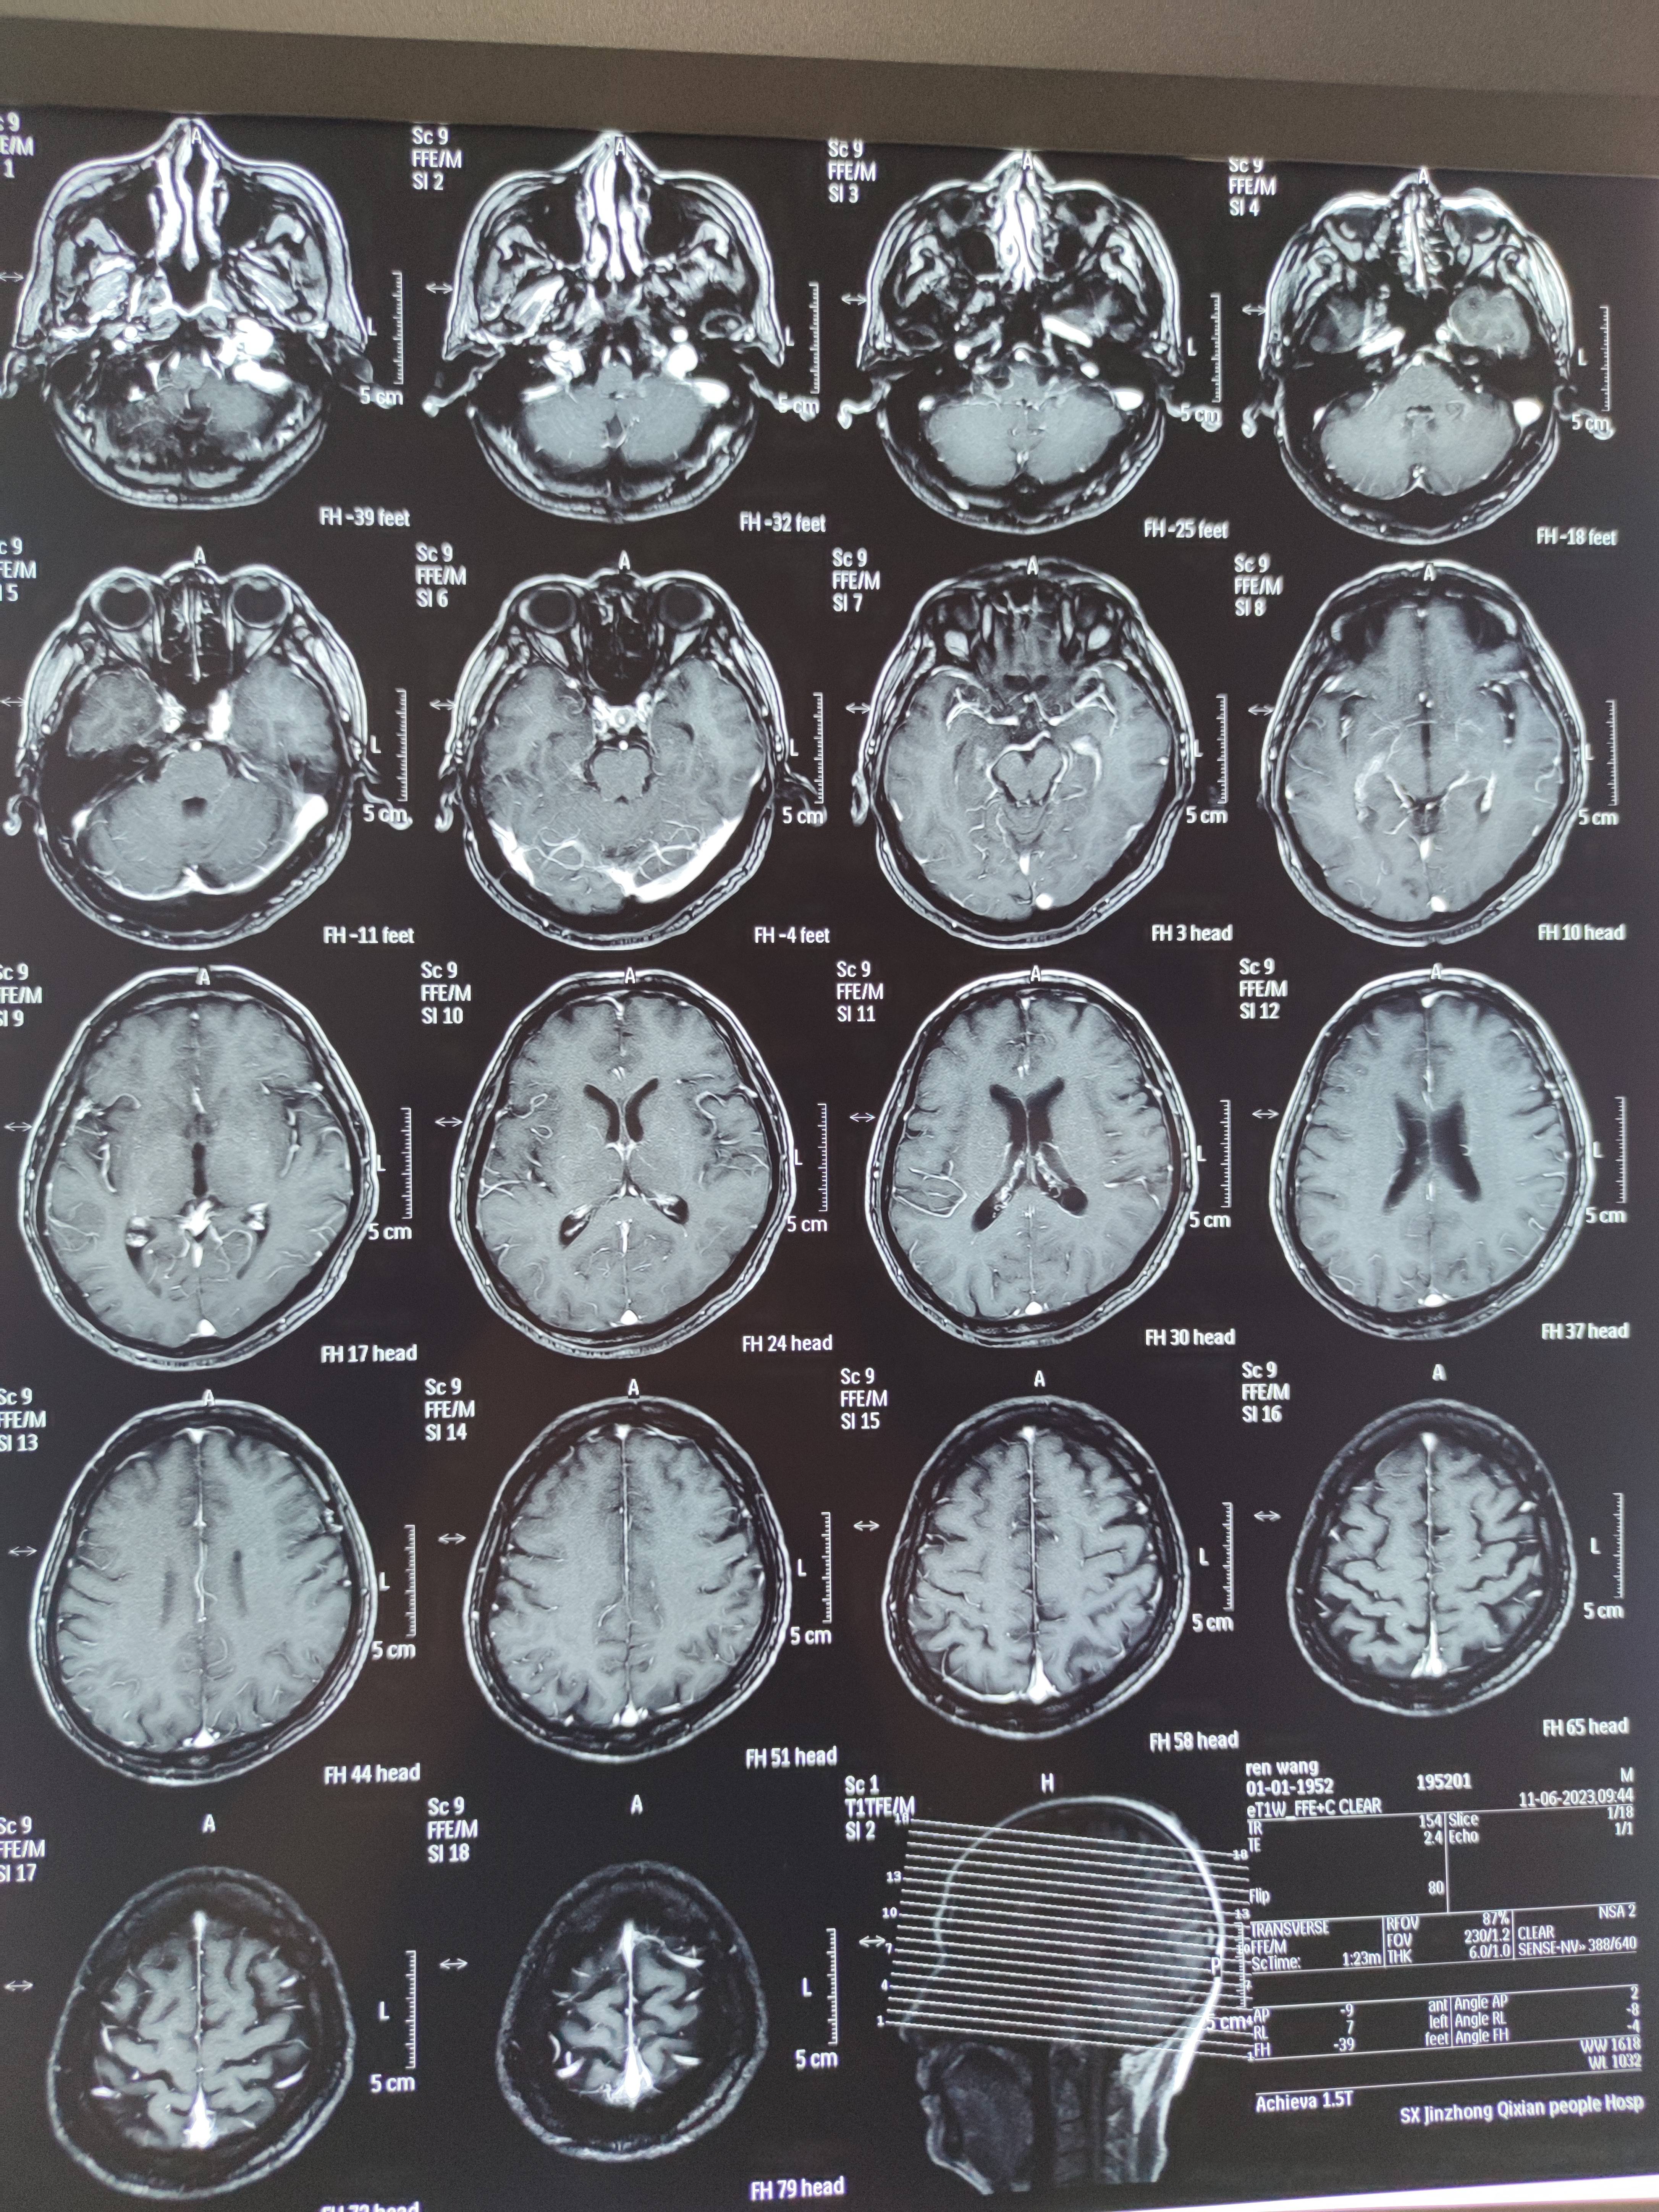

四月份癌胚抗原还是5.6,这个月到8了,持续升高。做了核磁增强,左侧桥小脑角哪有个地方不确定。肝脏核磁平扫弥散有两个点状高信号,转移也排不了,胃肠镜正常,左颈部有个变圆的淋巴结,保险点是不该加个化疗药了?咨询了陈波主任,等结果的吧!图片